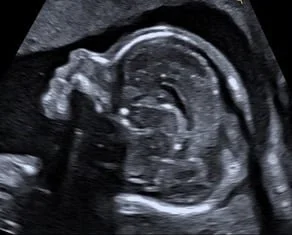

Herzschlag eines Feten im 3. Schwangerschaftsdrittel

Ich arbeite mit einem „High-End-Ultraschallgerät“ der neuesten Generation, welches speziell für Pränataldiagnostik und Frauenheilkunde entwickelt wurde.